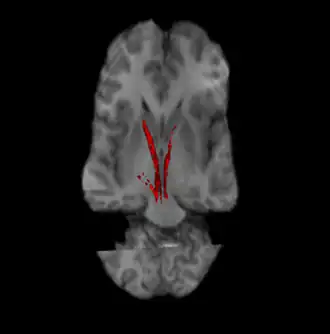

Nigrostriatal pathway (Left and Right in red).

The nigrostriatal pathway is a bilateral dopaminergic pathway in the brain that connects the substantia nigra pars compacta (SNc) in the midbrain with the dorsal striatum (i.e., the caudate nucleus and putamen) in the forebrain. It is one of the four major dopamine pathways in the brain, and is critical in the production of movement as part of a system called the basal ganglia motor loop. Dopaminergic neurons of this pathway release dopamine from axon terminals that synapse onto GABAergic medium spiny neurons (MSNs), also known as spiny projection neurons (SPNs),[1][2] located in the striatum.